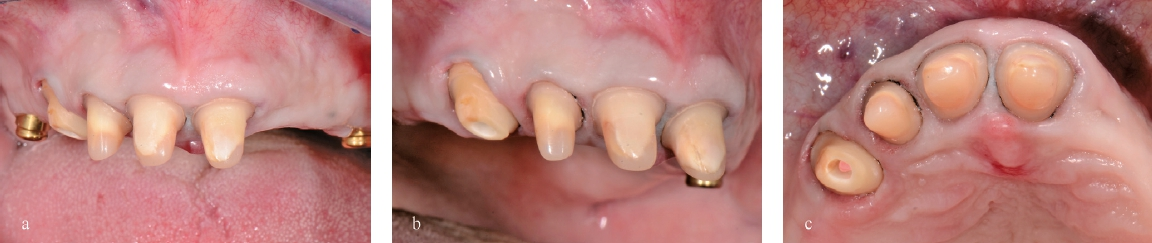

Während der Vorbehandlung sollte nebst der Extraktion des nicht erhaltungswürdigen Zahnes 22 und der Demontage der bestehenden verblockten Kronen 13-12-11-21 auch die fehlerhafte Ausrichtung der Okklusionsebene der bestehenden Versorgung korrigiert werden. Hierfür wurden Oberkiefer und Unterkiefer in das Therapiekonzept miteinbezogen. Mittels Verlängerung der Zähne im 1. und 3. Quadranten wurde eine Erhöhung der vertikalen Relation erzielt. Technisch erfolgte die Bisshebung mit einem neu angefertigten Drahtklammerprovisorium im Oberkiefer sowie indirekten Kompositaufbauten der Zähne 34, 35 und 36. Beide Therapieschritte wurden vor Fertigstellung in Wachs respektive als Mock-up einprobiert (Abb. 3). Anschließend wurden die verblockten Kronen 13-12- 11-21 demontiert und mittels Eierschalenprovisorien versorgt; Zahn 22 wurde extrahiert und die neu angefertigte Drahtklammerprothese im Oberkiefer sowie die indirekten Aufbauten im Unterkiefer eingegliedert (Abb. 4 u. 5). Eine weitere parodontale oder dentale Vorbehandlung war nicht notwendig.

Mittels Platzanalyse auf dem Modell wurde die notwendige Nachpräparation der Pfeilerzähne festgelegt und anschließend klinisch umgesetzt. Dentindefekte wurden vorher mit Komposit direkt aufgebaut (Abb. 10 u. 11). Es folgte eine einzeitig zweiphasige Meisterabformung der Pfeilerzähne mit PermadyneTM (3M, Neuss) und einem individuellen Löffel mit folgender Einprobe der Primärteile (Abb. 12–14).

In einem nächsten Schritt wurden die Primärteile provisorisch fixiert und zusammen mit den Implantaten und den Schleimhautarealen überabgeformt (ImpregumTM, 3M) zur Herstellung des Meistermodells (Abb. 15). Die Position der Implantate wurde mittels „Verification Stent“ rückkontrolliert und die vertikale und horizontale Kieferrelation intraoral mittels Handbissnahme verschlüsselt. Aufgrund der nicht unerheblichen Achsendivergenz zwischen den Implantaten und den natürlichen Pfeilerzähnen wurde entschieden, die Implantate anstelle von konfektionierten Einzelelementen mit individuellen CAD/CAM-Teleskopkronen (Atlantis Abutments, Dentsply Sirona, Wals bei Salzburg, Österreich) zu versorgen. Konfektionierte Einzelelemente wären durch die Achsendivergenz einem erhöhten Verschleiß unterzogen gewesen, was wiederum mit einem gesteigerten Nachsorgebedarf verbunden gewesen wäre. Nach mehreren Set-up-Einproben konnte schließlich auch das Sekundärgerüst hergestellt werden. Sämtliche Sekundärteile wurden dabei als Vollgussteile designt und mit dem Modellgussgerüst verklebt, mit Ausnahme der Sekundärteile für die Implantatteleskopkronen, welche zur Sicherstellung der Passivität intraoral verklebt werden sollten (Abb. 16 u. 17). Sowohl Primär- als auch Sekundärteile wurden für eine höhere Härte während 30 min bei 400°C vergütet. Anschließend konnte das geschlüsselte Set-up und auf das Gerüst aufgepasst werden. Um die Pfeilerzähne wurde die Prothese offen gestaltet, um eine natürliche Umspülung der Pfeilerzähne zu ermöglichen. Auf ein Palatinalband konnte aufgrund der guten Kammverhältnisse und des breiten Unterstützungspolygons verzichtet werden. Nach einer letzten klinischen Einprobe konnte die Prothese durch den Zahntechniker individualisiert und fertiggestellt werden (Abb. 18).